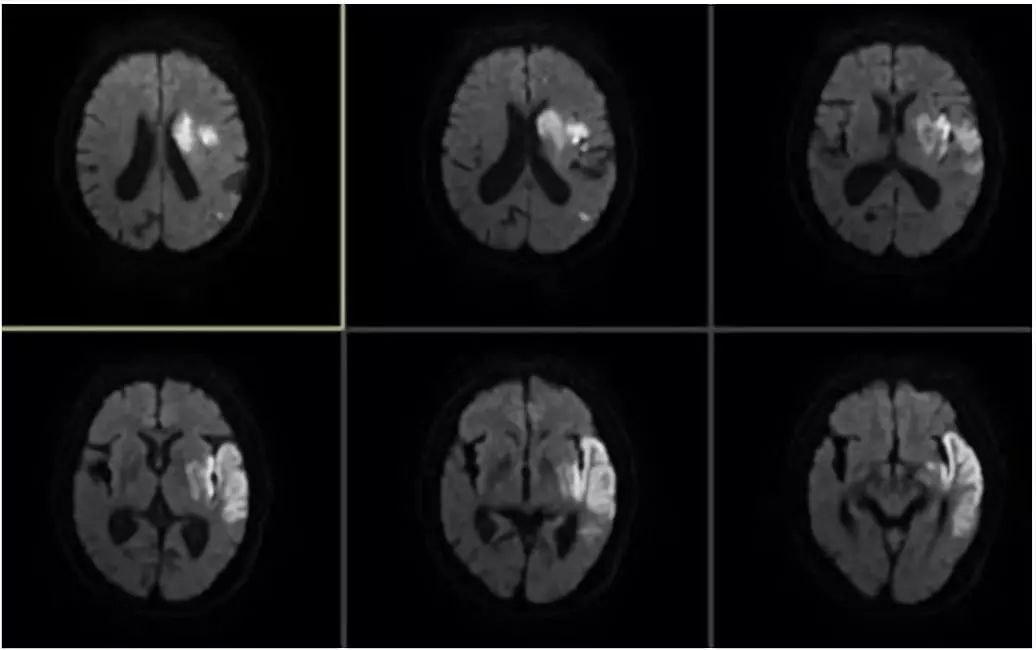

术后复查头颅平扫CT可见左侧基底节区局部造影剂停留(图8)

图8

术后复查头MRI示(图9)

图9

患者术后替罗非班泵入24小时,再过度使用阿斯匹林100mg、氯吡格雷75mg抗栓及瑞舒伐他汀20mg口服强化降脂稳定斑块治疗。术后第3天,患者肢体无力症状恢复正常,混合性失语症状较前好转,NIHSS评分:2分。术后90天门诊随诊时,遗留轻度失语,mRS评分1分。